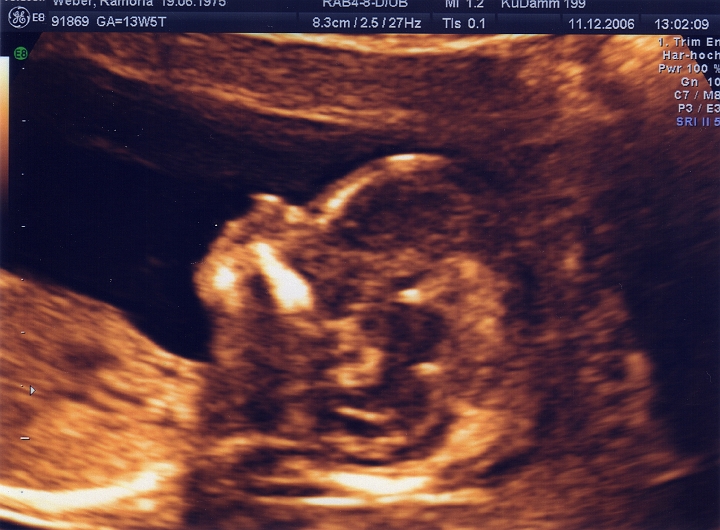

14. SSW - und das Köpfchen ist schon so gut zu erkennen !